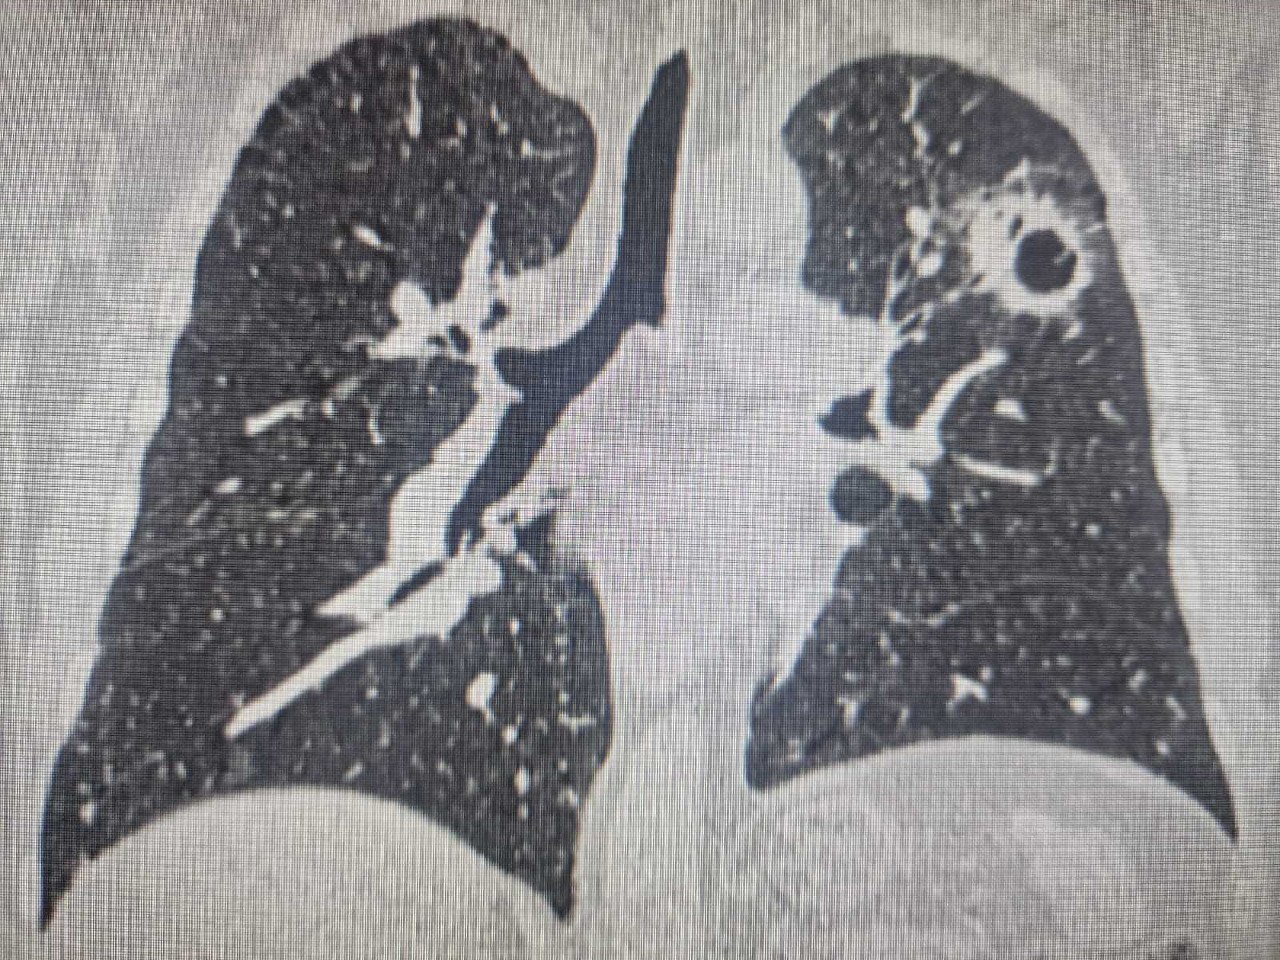

Новосибирец трижды заболел раком, две опухоли были в легких

Во время первой операции хирурги-онкологи сохранили легкое, убрав пораженный сегмент. Только поэтому пациенту смогли прооперировать через год второе легкое, в котором позже обнаружили еще один очаг.

Более того, у этого пациента между первой и второй операцией на легком выявился еще рак щитовидной железы. Ему удалили щитовидную железу, потом он прошел радиойодтерапию. После последней операции в течение года у пациента была ремиссия. Но, к сожалению, рак начал прогрессировать. Сейчас пациент находится на химиотерапии.